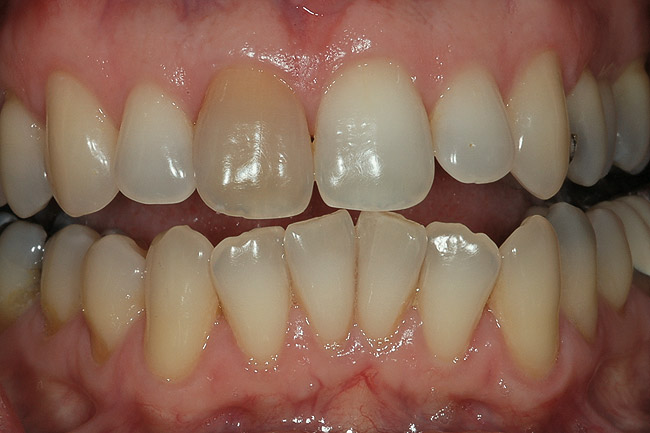

Figure 10  This root canal has been successful for 30 years, but the tooth has become slightly discolored. There is no reason from the radiograph to re-enter the pulp chamber, as this will further weaken the tooth. External bleaching by a single-tooth bleaching tray is indicated.

Figure 10

Figure 11  The 10% carbamide peroxide bleaching material was applied externally with the single-tooth bleaching tray nightly until the shade of the endodontically treated tooth returned to match the adjacent teeth. Should the tooth re-darken again, the process can be repeated without danger to the tooth. Figure 10 and Figure 11 courtesy of Meigan Johnson.

Figure 11